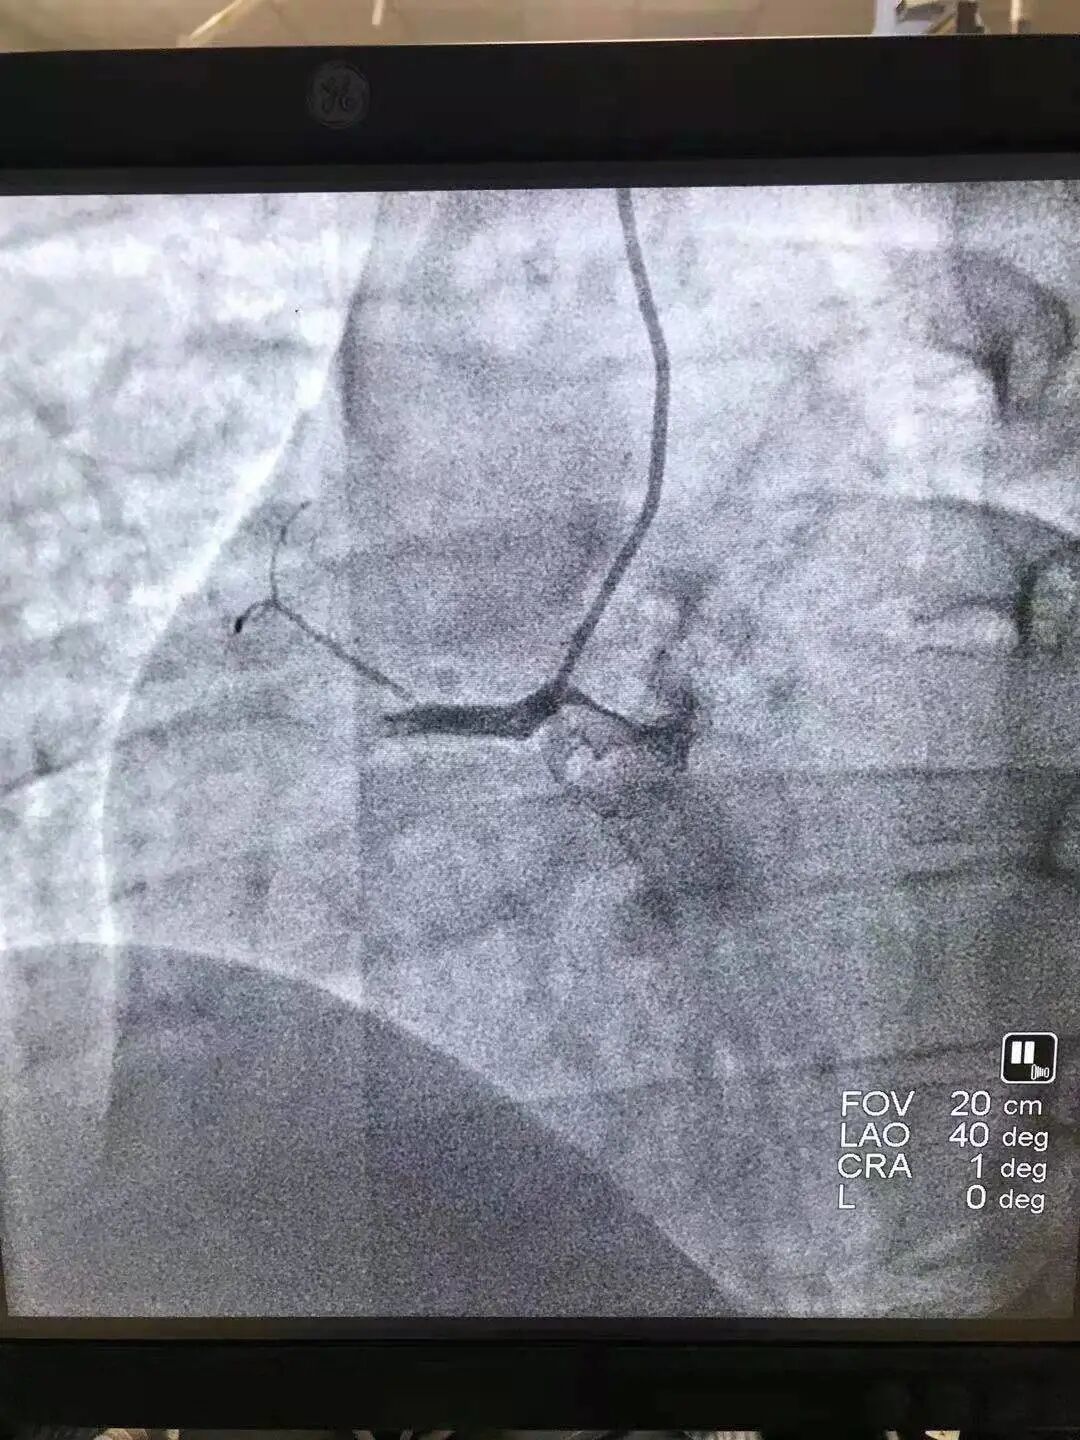

曲伟医生在造影中发现患者右侧冠脉完全闭塞,按照急症处理,给予冠脉介入治疗,迅速开通血管,从上手术台到手术结束不到40分钟,就成功把患者从死亡边缘拽了回来!

手术后